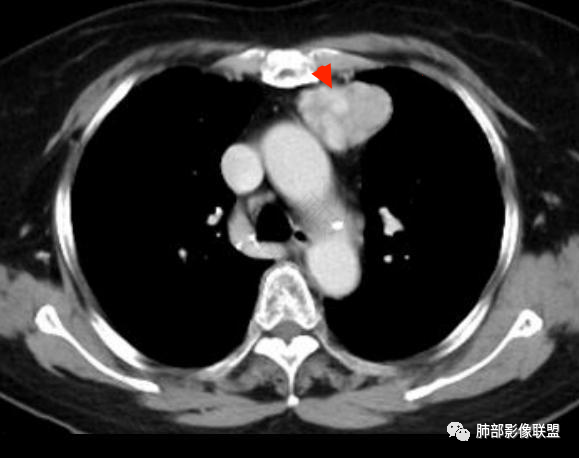

左侧前纵膈肿块,分叶状,边缘清晰,密度不均,内可见低密度坏死及纤维分隔,明显强化,左侧内乳动脉供血,常规考虑胸腺瘤,鉴别副节瘤

老年女性,前上纵隔偏左占位,边界清楚,分叶,内有纤维分隔,左侧内乳动脉稍增粗,首先考虑AB型胸腺瘤,鉴别CD或副节瘤